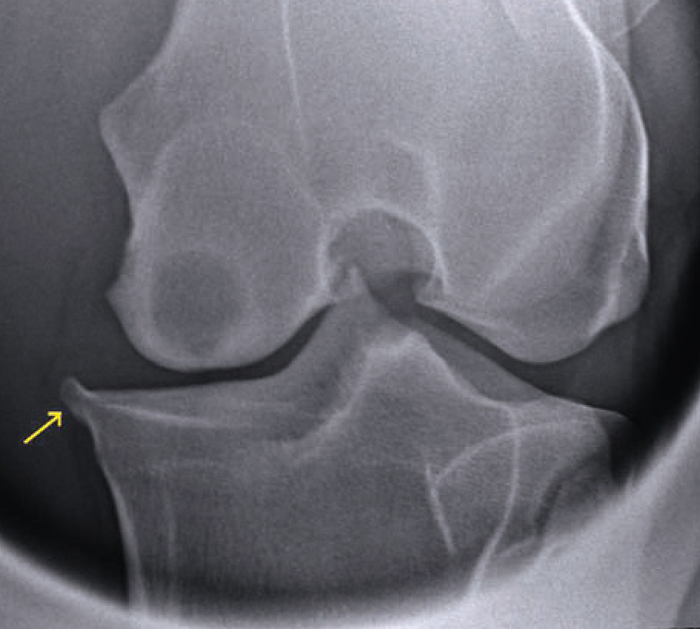

Figure 2 from Radiographic localisation of the entheses of the equine

Figure 2 from Radiographic localisation of the entheses of the equine Equine Stifle Arthritis Injuries of the meniscus most. much of what we know about soft tissue injuries in the stifle has come from observations during diagnostic investigation of lame horses using arthroscopy. the stifle is made up of the femorotibial and femoropatellar joints. Signs of arthritis in horses. when an equine veterinarian rehabilitates an injured stifle, he or she has. Equine Stifle Arthritis.